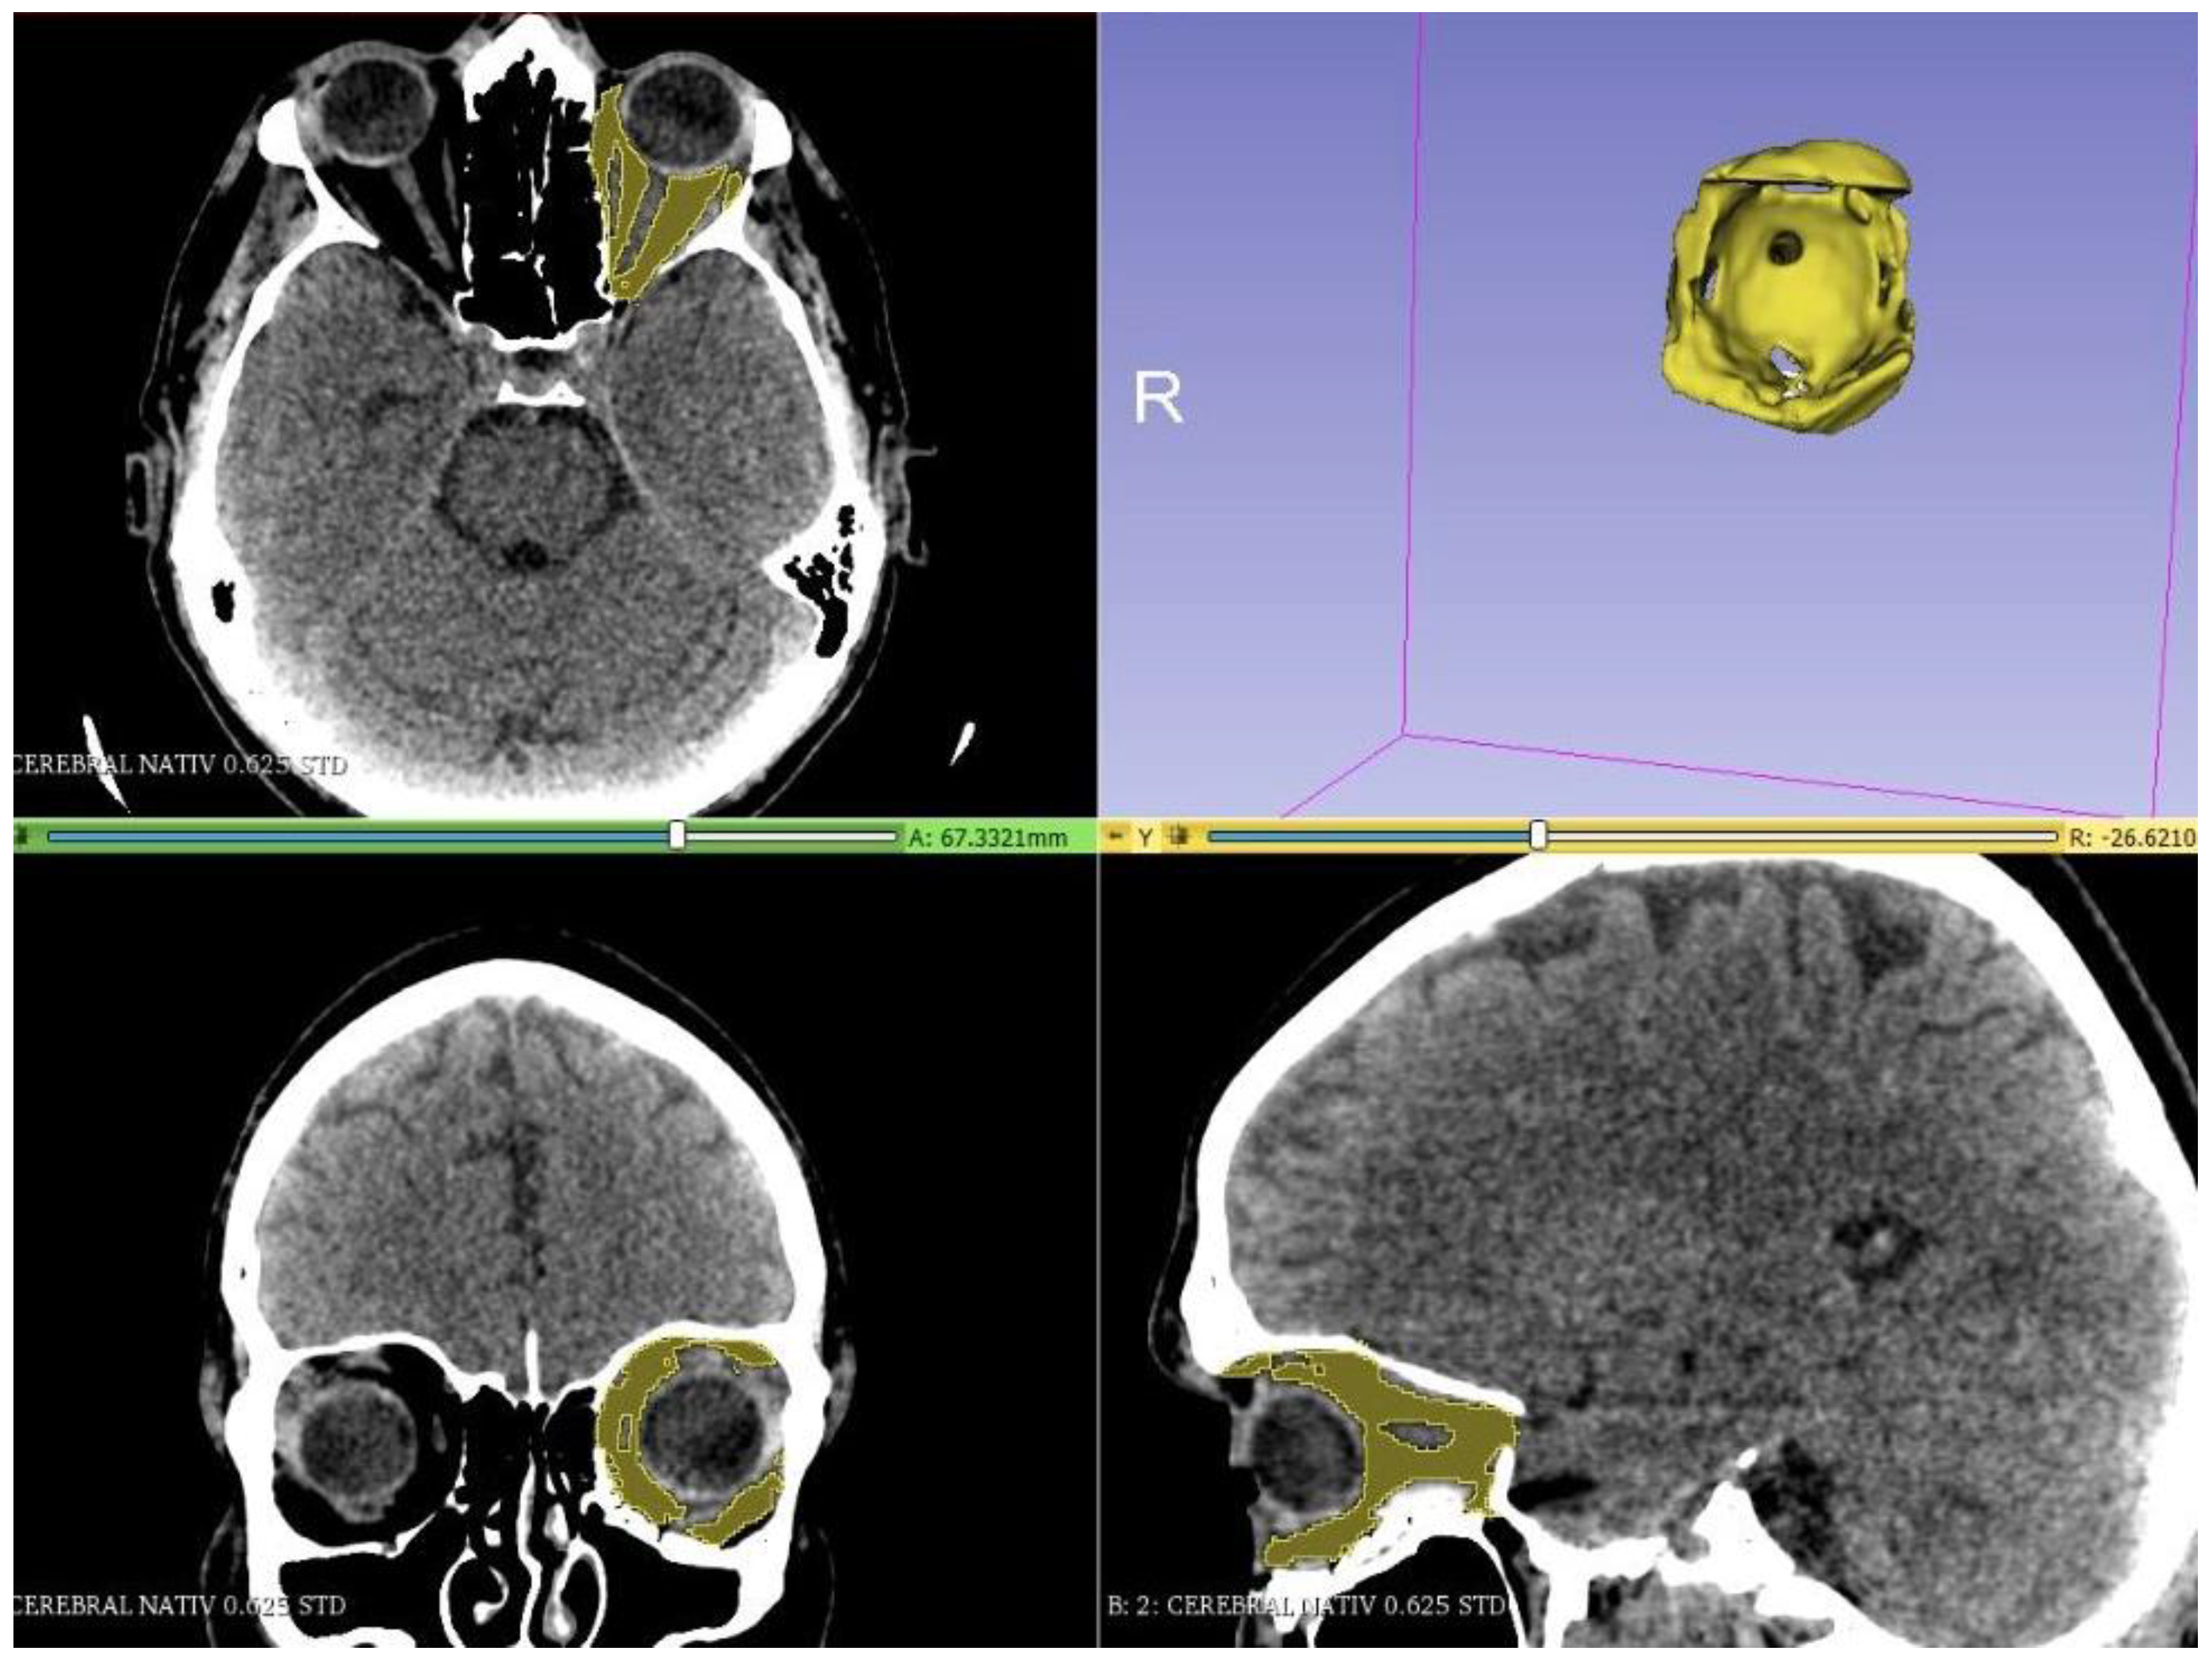

2. Materials and Methods

3. Results